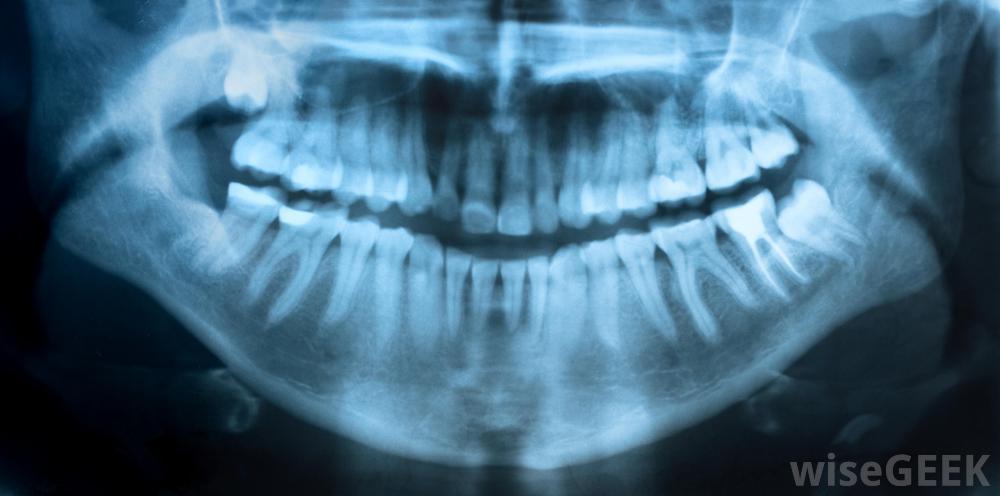

妇女在怀孕期间对根管的主要担忧可能是需要x光片。然而,在大多数情况下,对正在发育中的孩子的风险是最小的。进行根管治疗所需的x光片是针对妇女的口腔而不是腹部,因为这可能会影响到她的宝宝。此外,如果妇女怀孕期间需要x光片,牙医可能会提供一件铅背心来保护她的腹部尽管如此,牙医通常建议妇女等到分娩后才进行常规x光检查;只有那些对根管或其他牙科手术绝对必要的检查通常在怀孕期间进行。

数字放射技术允许牙医对患者进行x光检查;牙齿不会暴露在危险的辐射水平下。